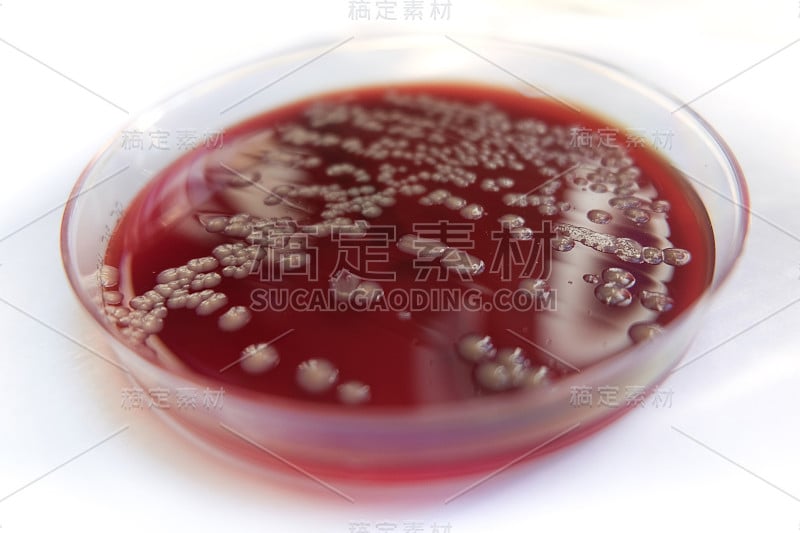

培养基板上的细菌菌落详情

JPG